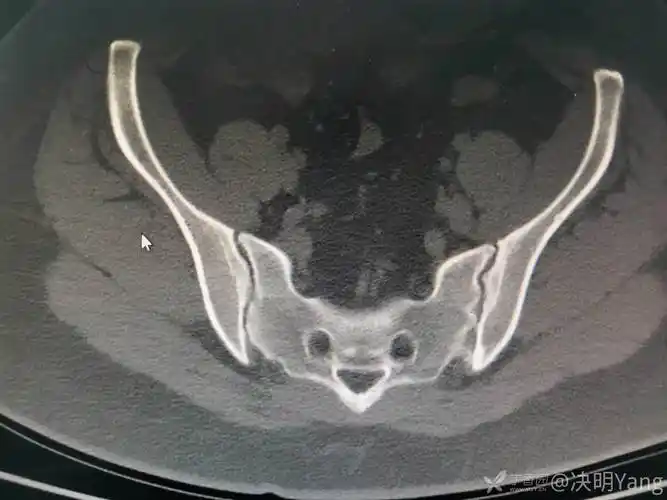

各位老师基层医院经验有限烦请各位可否指教这几张骶髂关节ct图像